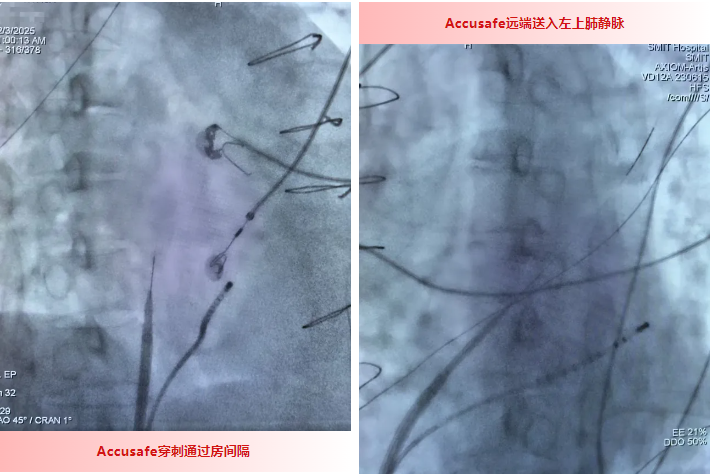

为保障手术安全高效开展,刘燕锋博士带领团队反复研讨,最终决定采用新型器械组合——Accusafe房间隔穿刺导丝搭配可调弯鞘,实施safe2优化的房间隔穿刺术。

与家属和病人充分沟通后,手术如约举行,在X线透视的精准引导下,手术团队凭借丰富的临床经验与精湛技术,快速完成可调弯鞘内芯的定位与角度调整,精准找到最佳穿刺位置。随后送入房间隔穿刺导丝,导丝轻松突破增厚的房间隔进入左心房,其特殊设计还同步规避了组织误伤风险;紧接着刘燕锋博士带领团队继续稳步推进操作,顺利导引可调弯鞘进入左心房。整个穿刺过程一气呵成,操作精准娴熟、流程流畅高效,成功攻克了这一高难度技术难题!